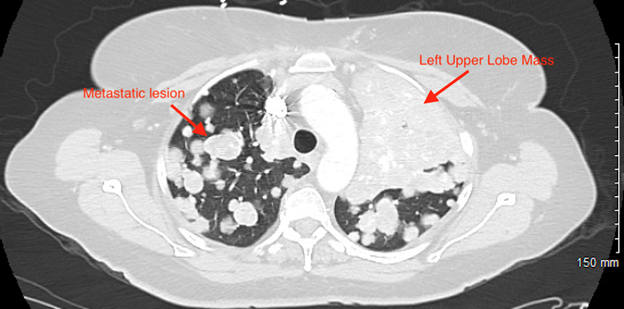

the left upper lobe 10.5 x 8.2 x 11.3 cm

with

innumerable diffuse bilateral pulmonary metastatic appearing nodules with areas

of nodular conglomeration (Figures 2 and

Figure 2: Areas of

Pulmonary Metastasis with a Large Mass in Upper Lung Lobe